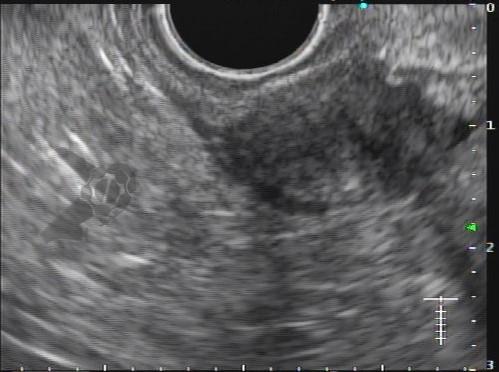

Figuras 1 e 2. Imagem endoscópica em visão direta de lesão protrusa entre pequena curvatura e parede posterior de corpo gástrico proximal, revestida por mucosa com superfície regular, normocorada e íntegra. A imagem ecoendoscópica demonstra lesão com ecogenicidade hipoecoica, ecotextura homogênea, formato ovalado, sem características internas, sem vascularização ao doppler, limites precisos, contornos regulares, medindo aproximadamente 20 x 6 mm e inserida em camada muscular própria. Punções ecoguiadas foram realizadas com agulha FNB, sendo o anatomopatológico e imuno-histoquímica compatíveis com GIST gástrico. Fonte: arquivos do Instituto do Câncer do Estado de São Paulo (ICESP/HCFMUSP)Figuras 1 e 2. Imagem endoscópica em visão direta de lesão protrusa entre pequena curvatura e parede posterior de corpo gástrico proximal, revestida por mucosa com superfície regular, normocorada e íntegra. A imagem ecoendoscópica demonstra lesão com ecogenicidade hipoecoica, ecotextura homogênea, formato ovalado, sem características internas, sem vascularização ao doppler, limites precisos, contornos regulares, medindo aproximadamente 20 x 6 mm e inserida em camada muscular própria. Punções ecoguiadas foram realizadas com agulha FNB, sendo o anatomopatológico e imuno-histoquímica compatíveis com GIST gástrico. Fonte: arquivos do Instituto do Câncer do Estado de São Paulo (ICESP/HCFMUSP)Figuras 3 e 4. Imagem endoscópica em visão direta de abaulamento de parede em segunda porção duodenal distalmente à papila duodenal maior, revestida por mucosa com íntegra, de coloração amarelada e superfície regular. A ecoendoscopia demonstra lesão com ecogenicidade hiperecoica, ecotextura homogênea, formato arredondado, medindo cerca de 10 mm no maior eixo, com limites precisos, contornos regulares, medindo cerca de 10 mm no maior diâmetro e inserida em camada submucosa, sendo os achados endoscópicos e ecoendoscópicos compatíveis com lipoma.Figuras 3 e 4. Imagem endoscópica em visão direta de abaulamento de parede em segunda porção duodenal distalmente à papila duodenal maior, revestida por mucosa com íntegra, de coloração amarelada e superfície regular. A ecoendoscopia demonstra lesão com ecogenicidade hiperecoica, ecotextura homogênea, formato arredondado, medindo cerca de 10 mm no maior eixo, com limites precisos, contornos regulares, medindo cerca de 10 mm no maior diâmetro e inserida em camada submucosa, sendo os achados endoscópicos e ecoendoscópicos compatíveis com lipoma.Fig. 5. Imagem endoscópica em visão direta de lesão protrusa em parede anterior de antro gástrico proximal, revestida por mucosa normocorada, com superfície regular, sendo sugestiva de lesão subepitelial.Fig. 6. A ecoendoscopia evidencia lesão com ecogenicidade hipoecoica, ecotextura predominantemente homogênea, formato arredondado, limites precisos, bordos regulares, medindo aproximadamente 13,4 x 12 mm, sem focos hiperecoicos ou calcificações no interior e inserida na camada muscular própria. Punções ecoguiadas foram realizadas com agulha FNB, sendo anatomopatológico e imuno-histoquímica confirmando schwanomma gástrico.Fig. 7 e 8. Imagem de esofagogastroduodenoscopia demonstra lesão protrusa em papila duodenal maior revestida por mucosa enantemática e com superfície com três erosões recobertas por fibrina.Fig. 7 e 8. Imagem de esofagogastroduodenoscopia demonstra lesão protrusa em papila duodenal maior revestida por mucosa enantemática e com superfície com três erosões recobertas por fibrina.Fig. 9 e 10. Imagem à ecoendoscopia demonstra lesão com formato ovalado, ecogenicidade hipoecoica, ecotextura heterogênea, com contornos regulares, sem adenopatia adjacente, sem vascularização ao doppler, sem características internas, medindo cerca de 20 x 11 x 24 mm, inserida na camada submucosa, não havendo acometimento da muscular própria. Foram realizadas punções ecoguiadas com agulha FNA 22 gauge, sendo o anatomopatológico e imunohistoquímica compatíveis com tumor neuroendócrino de papila duodenal bem diferenciado grau 1.Fig. 9 e 10. Imagem à ecoendoscopia demonstra lesão com formato ovalado, ecogenicidade hipoecoica, ecotextura heterogênea, com contornos regulares, sem adenopatia adjacente, sem vascularização ao doppler, sem características internas, medindo cerca de 20 x 11 x 24 mm, inserida na camada submucosa, não havendo acometimento da muscular própria. Foram realizadas punções ecoguiadas com agulha FNA 22 gauge, sendo o anatomopatológico e imunohistoquímica compatíveis com tumor neuroendócrino de papila duodenal bem diferenciado grau 1.Fig. 11 e 12. Esofagogastroduodenoscopia demonstra abaulamento de parede anterior de corpo gástrico proximal, com mucosa normocorada, superfície regular com depressão central, sendo compatível com lesão subepitelialFig. 11 e 12. Esofagogastroduodenoscopia demonstra abaulamento de parede anterior de corpo gástrico proximal, com mucosa normocorada, superfície regular com depressão central, sendo compatível com lesão subepitelialFig. 13 e 14. Ecoendoscopia demonstrou formação com ecogenicidade hipoecoica, ecotextura homogênea, formato ovalado, limites bem definidos, contornos regulares, medindo aproximadamente 13 mm e inserida na camada submucosa. Lesão foi submetida a ressecção endoscópica transmural com dispositivo FTRD. A histopatologia e imunohistoquímica confirmaram TNE gástrico bem diferenciado grau 2.Fig. 13 e 14. Ecoendoscopia demonstrou formação com ecogenicidade hipoecoica, ecotextura homogênea, formato ovalado, limites bem definidos, contornos regulares, medindo aproximadamente 13 mm e inserida na camada submucosa. Lesão foi submetida a ressecção endoscópica transmural com dispositivo FTRD. A histopatologia e imunohistoquímica confirmaram TNE gástrico bem diferenciado grau 2.